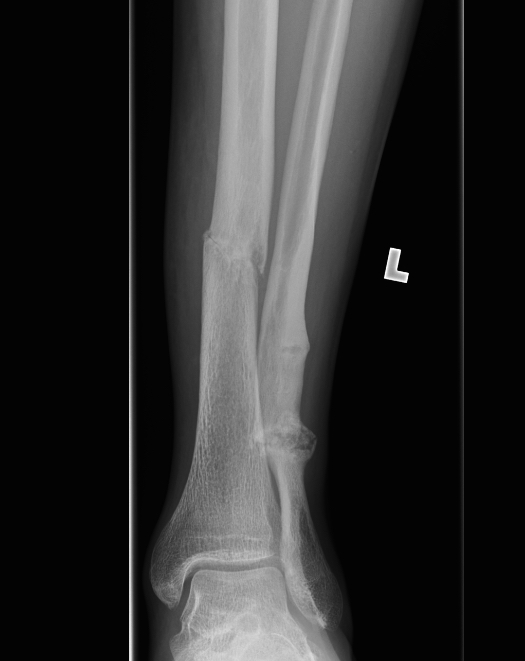

Xray

Cortical thickening

Look for "dreaded black line" - sign of fracture

Periosteal thickening with possible "dreaded black line"

Anterior cortical thickening with dreaded black line